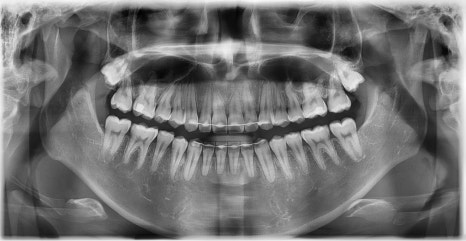

치료 전후 파노라마 비교 - 연세정원치과

돌출을 조금 더 개선하는 것을 추천했으나, 환자가 갑자기 군 입대를 하게 되어 현 상태로 치료를 마무리하기로 하였습니다. 치료 전후 치아 위아래 중심선이 일치하며 좌우 어금니 교합도 향상되었습니다. 하악 치열의 후방 이동으로 아래 입술의 돌출도도 많이 개선되었습니다. 멀리서도 믿고 내원해주고, 치료 기간 동안 성실히 협조해준 환자분께 감사드리며 앞으로도 건강한 치아로 군 생활 잘 마치길 응원합니다 :)

약 1년 간의 교정 치료를 통해 어긋나 있던 치아 중심선이 자연스럽게 맞춰졌고, 중심선 비대칭이 개선 및 하악 아랫입술 돌출도 눈에 띄게 호전되었습니다. 무엇보다 치료 기간 동안 앞니의 치근 흡수는 추가적인 진행 없이 안정적으로 유지되었습니다.